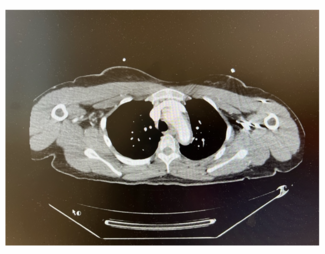

Takayasu arteritis (TA) is an inflammatory condition involving the aorta and its principal branches that leads to vessel stenosis and occlusion. To the authors' knowledge, this is the first case of TA treated with TCAR.